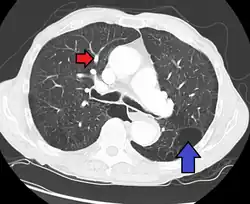

Diagnóstico

Uma avaliação diagnostica completa inclui uma historia, exame físico, radiografia de tórax, provas de função pulmonar, eletrocardiograma (ECG), ecocardiograma, imageamento de ventilação perfusão e cateterismo cardíaco. Em alguns casos, pode ser necessária uma biopsia pulmonar, realizada por toracoscopia, visando elaborar um diagnóstico definitivo. O cateterismo cardíaco do lado direito do coração revela a pressão arterial pulmonar elevada. Um ecocardiograma pode avaliar a progressão da doença e excluir outras condições com sinais e sintomas similares.

Uma cintilografia da ventilação-perfusão ou angiografia pulmonar. As provas de função pulmonar podem estar normais ou mostrar discreta diminuição na capacidade vital (CV) e na complacência pulmonar, com uma leve diminuição na capacidade de difusão.